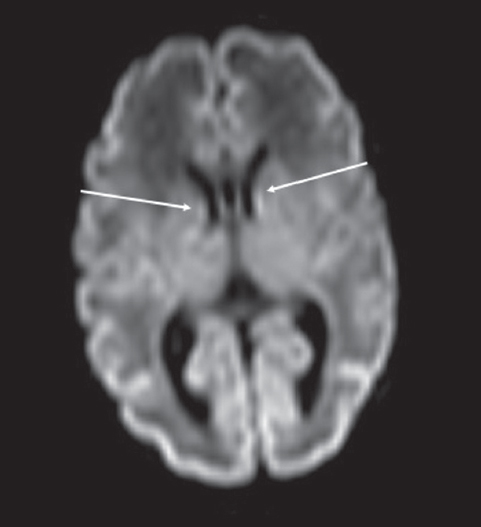

Как видно из таблицы, при выполнении МР-исследования в ПКВ 27–32 недели герминальный матрикс визуализировался у восьми недоношенных детей на ДВИ в виде усиления МР-сигнала вдоль боковых стенок боковых желудочков мозга, а также вдоль передних рогов над хвостатыми ядрами с обеих сторон (рис. 4). На Т2 ВИ герминальный матрикс достоверно выявлен у семи новорожденных (рис. 5). На Т1 ВИ герминальный матрикс достоверно выявлен у двух новорожденных (рис. 6). На последовательностях FLAIR герминальный матрикс не визуализировался.

Рис. 4. МРТ головного мозга недоношенного ребенка (ПКВ 28 недель), ДВИ, аксиальная проекция. Визуализируется гиперинтенсивный МР-сигнал от герминального матрикса в проекции наружных отделов боковых желудочков (отмечен стрелками)

Fig. 4. MRI of preterm newborn (PCA 28 wks.), DWI, axial plane. Hyperintensive MR-signal from the germinal matrix in the projection of the external parts of lateral ventricles (marked by arrows)

На ДВИ субэпендимальный герминальный матрикс выявляется у подавляющего числа недоношенных детей в возрастной группе 27–32 недели ПКВ, у двух недоношенных детей — в возрастной группе 33–34 недели ПКВ. Герминальный матрикс на ДВИ-последовательности визуализируется в виде локального гиперинтенсивного сигнала в области передних отделов боковых желудочков и гиперинтенсивного линейного сигнала в области наружного края боковых желудочков (частично повторяющего контур наружной стенки желудочка). Чувствительность ДВИ в визуализации герминального матрикса превышает другие импульсные последовательности МР и позволяет получить более полную визуализационную картину регрессии субэпендимального герминального матрикса в вентрикулярных зонах головного мозга недоношенных детей.